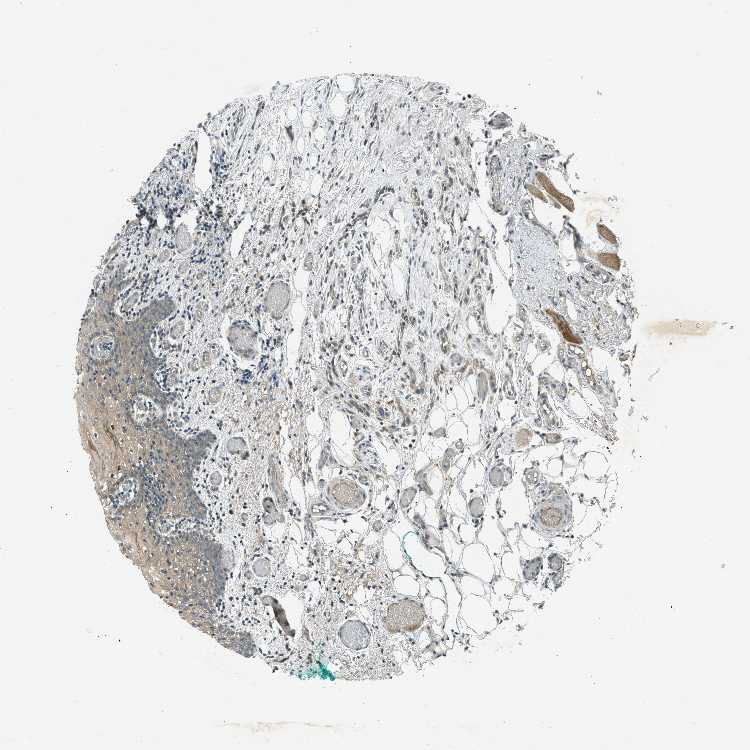

TISSUE PRIMARY DATA ORAL MUCOSA Show tissue menu

ORAL MUCOSA - Antibody stainingi

Antibody staining in the annotated cell types in the current human tissue is reported as not detected, low, medium, or high, based on conventional immunohistochemistry profiling in selected tissues. This score is based on the combination of the staining intensity and fraction of stained cells.

Each image is clickable and will lead to virtual microscopy that enables deeper exploration of all samples and also displays staining intensity scores, fraction scores and subcellular localization as well as patient and tissue information for each sample.

Antibody HPA017254Antibody CAB016231Antibody CAB022105

Squamous epithelial cells MediumNot detectedHigh